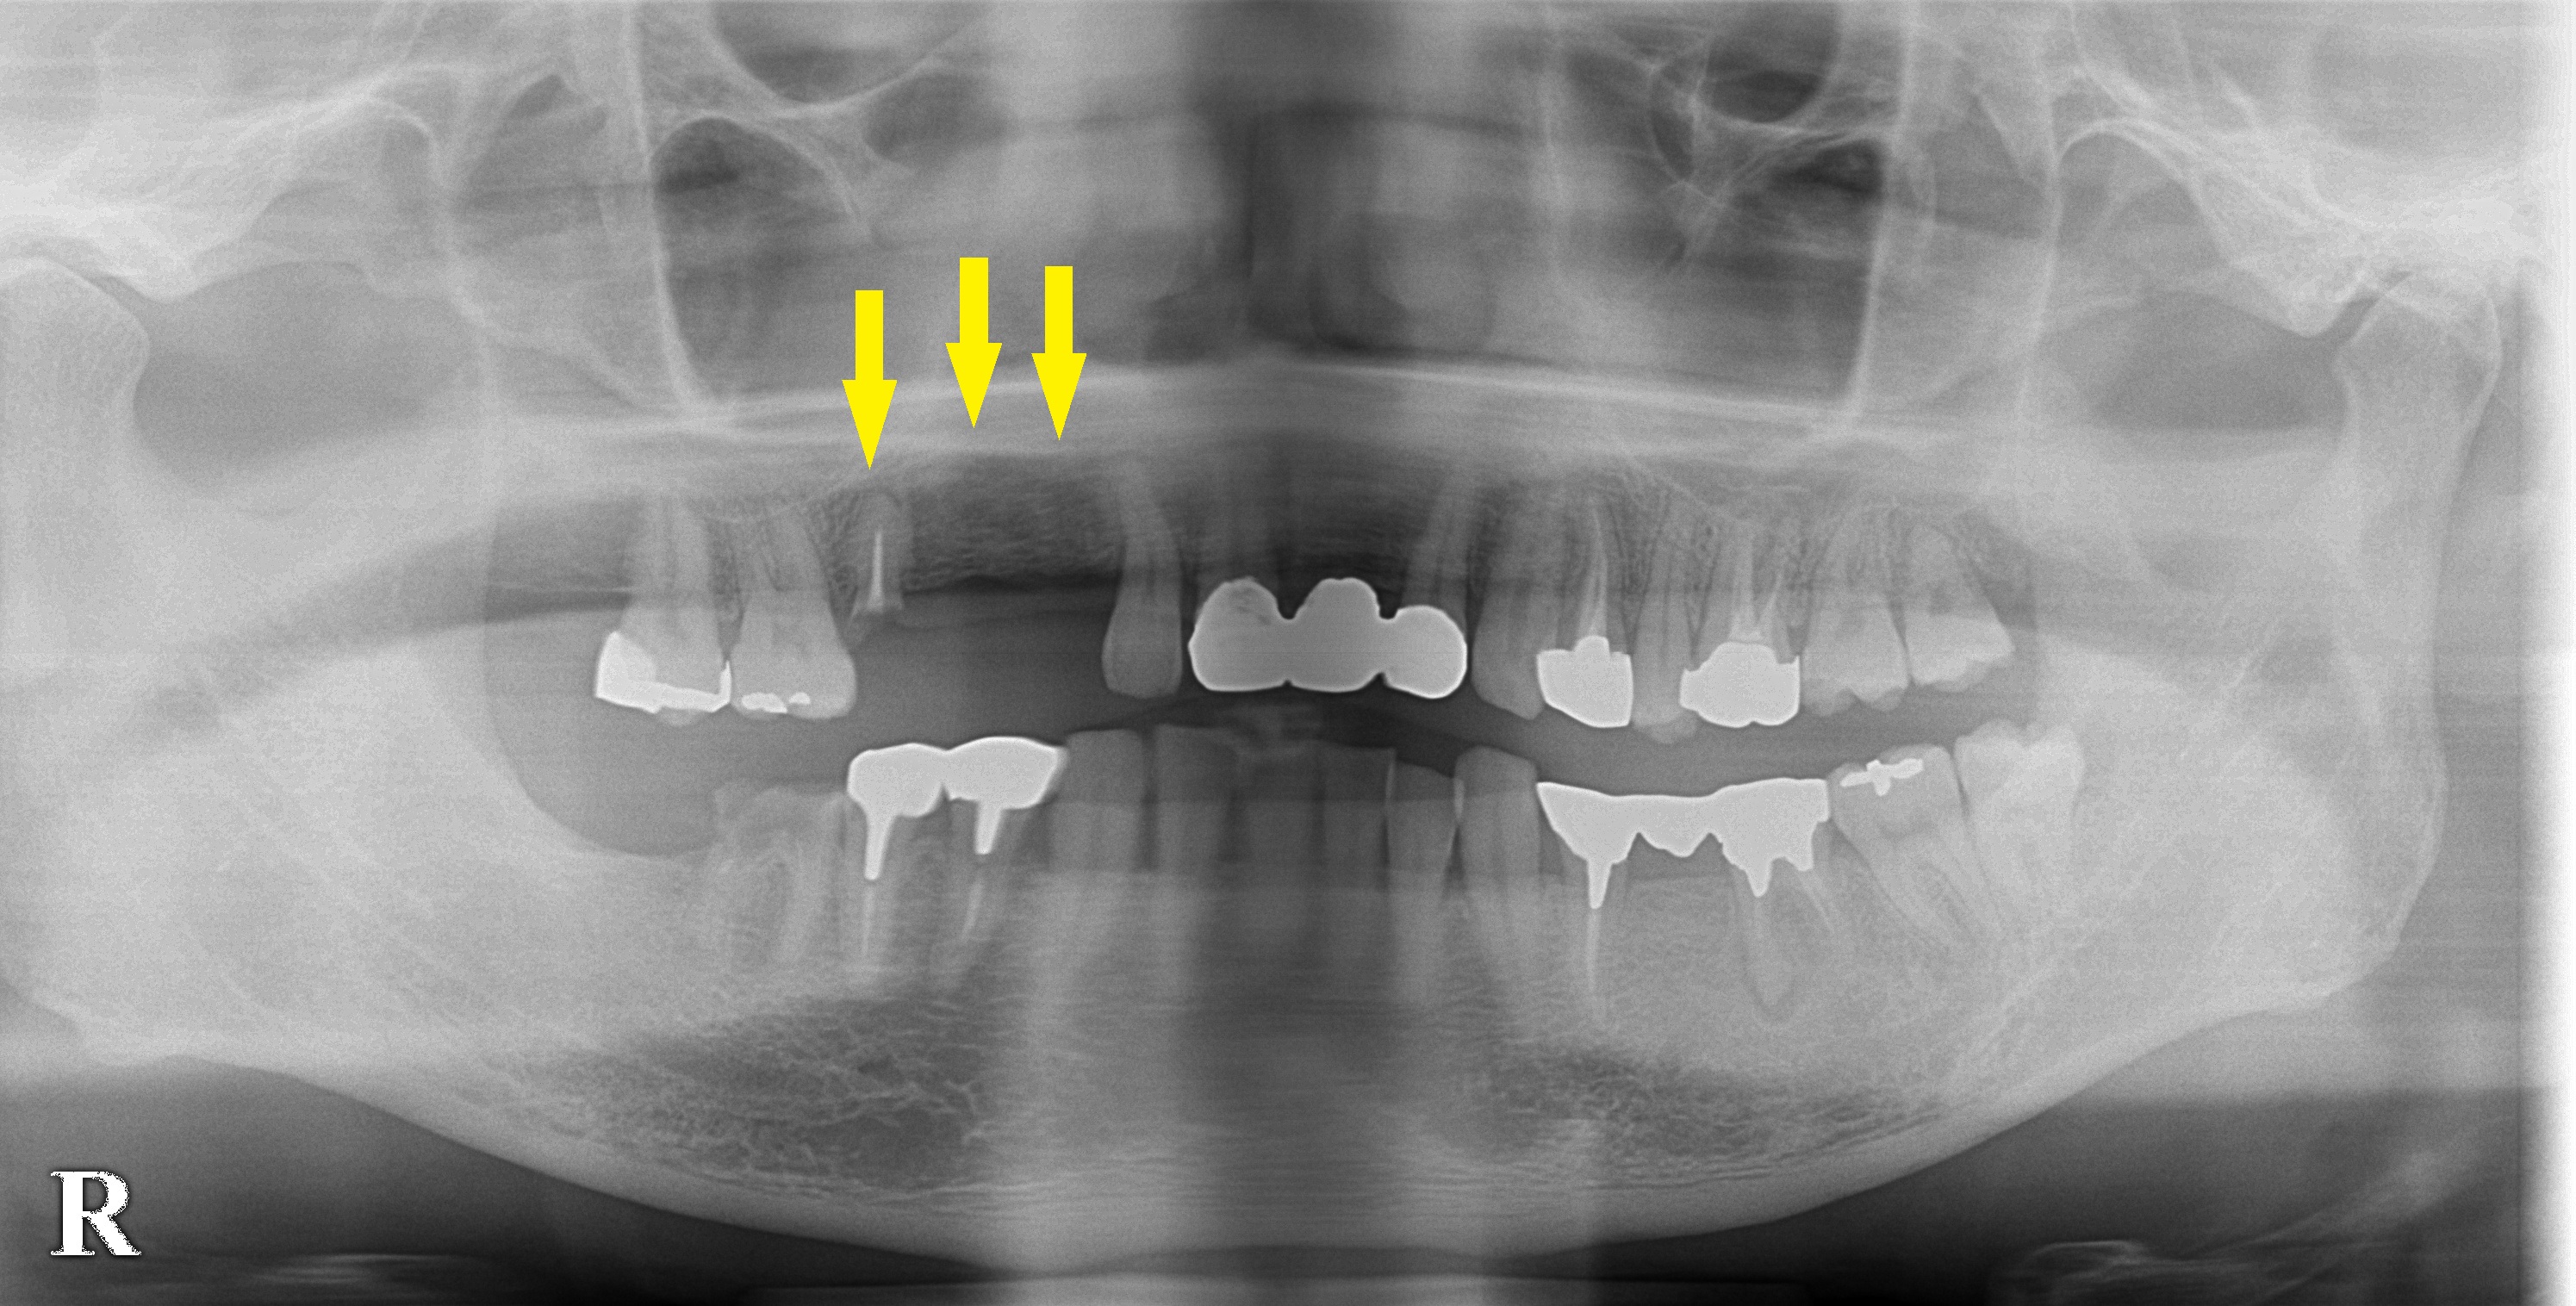

3歯のうち、レントゲン写真、CTにて、いちばん後方の歯は、骨が薄いことが判明したため、ソケットリフトという骨造成方法を併用する必要があることを説明させていただきました。

ご納得いただけたので、本日1か所ソケットリフトを合わせて行い右上顎にインプラント埋入術を施行しました。